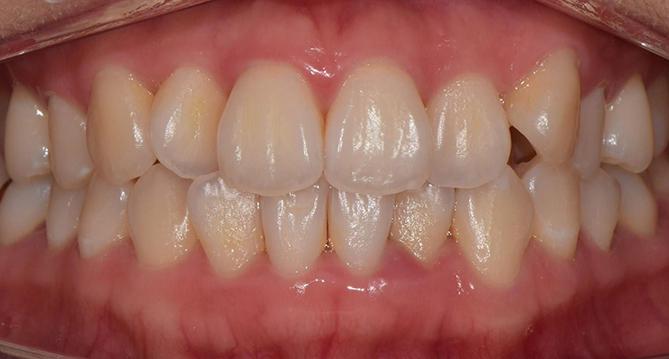

연세새빛치과 전체치아교정[클리피씨] 교정 전

연세새빛치과 전체치아교정[클리피씨] 교정 후